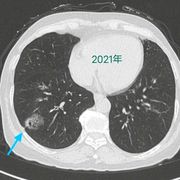

胸片是什么

胸片是影像学检查中的必备检查项目之一,因为其简单、方便操作的优势已经成为了日常临床工作中的首选检查。它可以帮助诊断出典型的肺部感染、肺结核以及肺部的...70250人收听

胸片就是普通x线胸部平片,一般都是拍胸部正位片。胸部正位片主要显示的是两侧的肺野,心影轮廓大小,胸椎,以及肋骨。作为影像科普通的检查,方便、快捷,为临床科室解决了许多常见的问题。比如...